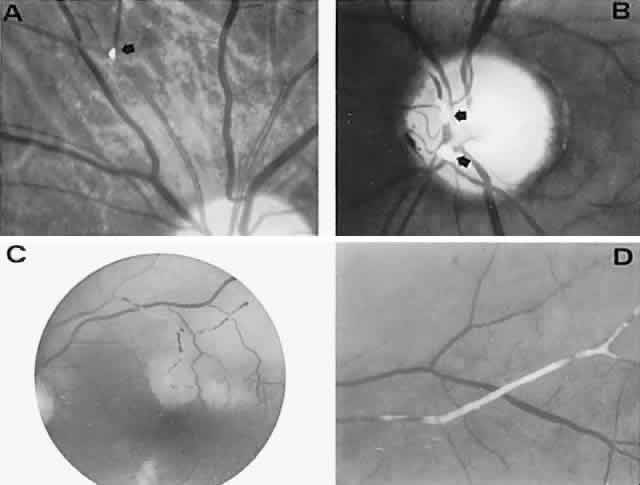

The retinal variety may be admixed in a person who suffers the more conventional attacks of migraine. It is presumed that vasospasm in the retinal circulation determines transient hypoxia, perhaps somewhat similar to the visual cortical event. On rare occasions, the fundus has been examined during typical retinal migraine episodes, and arterial constriction has been described. Wolter and Burchfield106 photographically documented such an episode and demonstrated mild “retinal edema”; vessel narrowing is also evident (Fig. 8). Fortunately, permanent complications of retinal migraine are rare. These may take the form of central retinal artery occlusion or ischemic papillopathy (see Volume 2, Chapter 16); nerve fiber bundle visual field defects may be demonstrated (Fig. 9).

Fig. 8. Retinal migraine. A. During amaurotic episode. Note the dusky appearance of the fundus, increased retinal sheen (possibly edema), and dark narrowed veins (arrows). The disc is also hyperemic. B. Fundus after episode. Compare paired arrows. (Courtesy of Dr. J. Reimer Wolter)

Fig. 9. An 18-year-old student with recurrent episodes of left retinal migraine. After a typical attack, he noted an inferior field defect. A. Fundus shows a defect in the superior arcuate nerve fiber bundle (between arrows: compare fiber layer below disc). B. Visual field defect corresponds to a retinal nerve fiber layer defect.